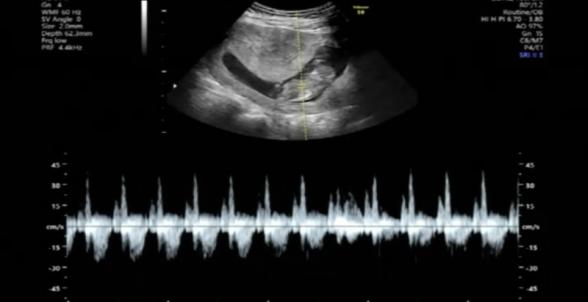

今のところ先生からの指摘はないですが、エコーでの心拍の様子はどうでしょうか?

逆流もあるようで心配です。

実際にどれぐらいの心拍数になるのか、逆流もどこの部分に見られるのかなど詳しいことは、こちらでもわからないところになってしまいます。